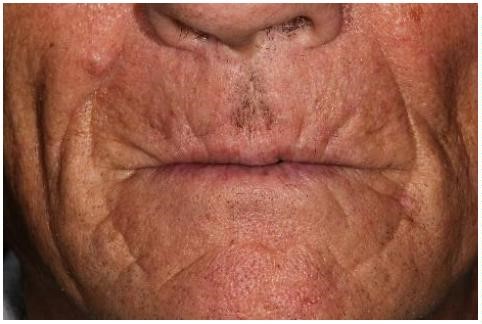

Durante la exploración clínica extraoral se observa la pérdida de la dimensión vertical, la presencia de arrugas peribucales y labios adelgazados debido a la ausencia total de piezas dentales (Figura 1). En la exploración

clínica intraoral se observa macroglosia, una avanzada e irregular reabsorción del hueso alveolar residual y escasa encía epitelizada (Figura 2).